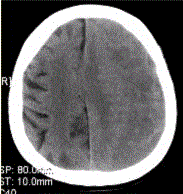

问题 患者男,70岁。突发昏迷。头CT显示如下图。 下列描述正确的是

选项 A.左侧额顶部硬膜下半月形混杂密度影 B.脑皮质未见异常 C.脑皮质受压内移 D.中线结构右移 E.脑实质异常密度影 F.右侧脑沟变窄

答案 ACD

解析 ACD